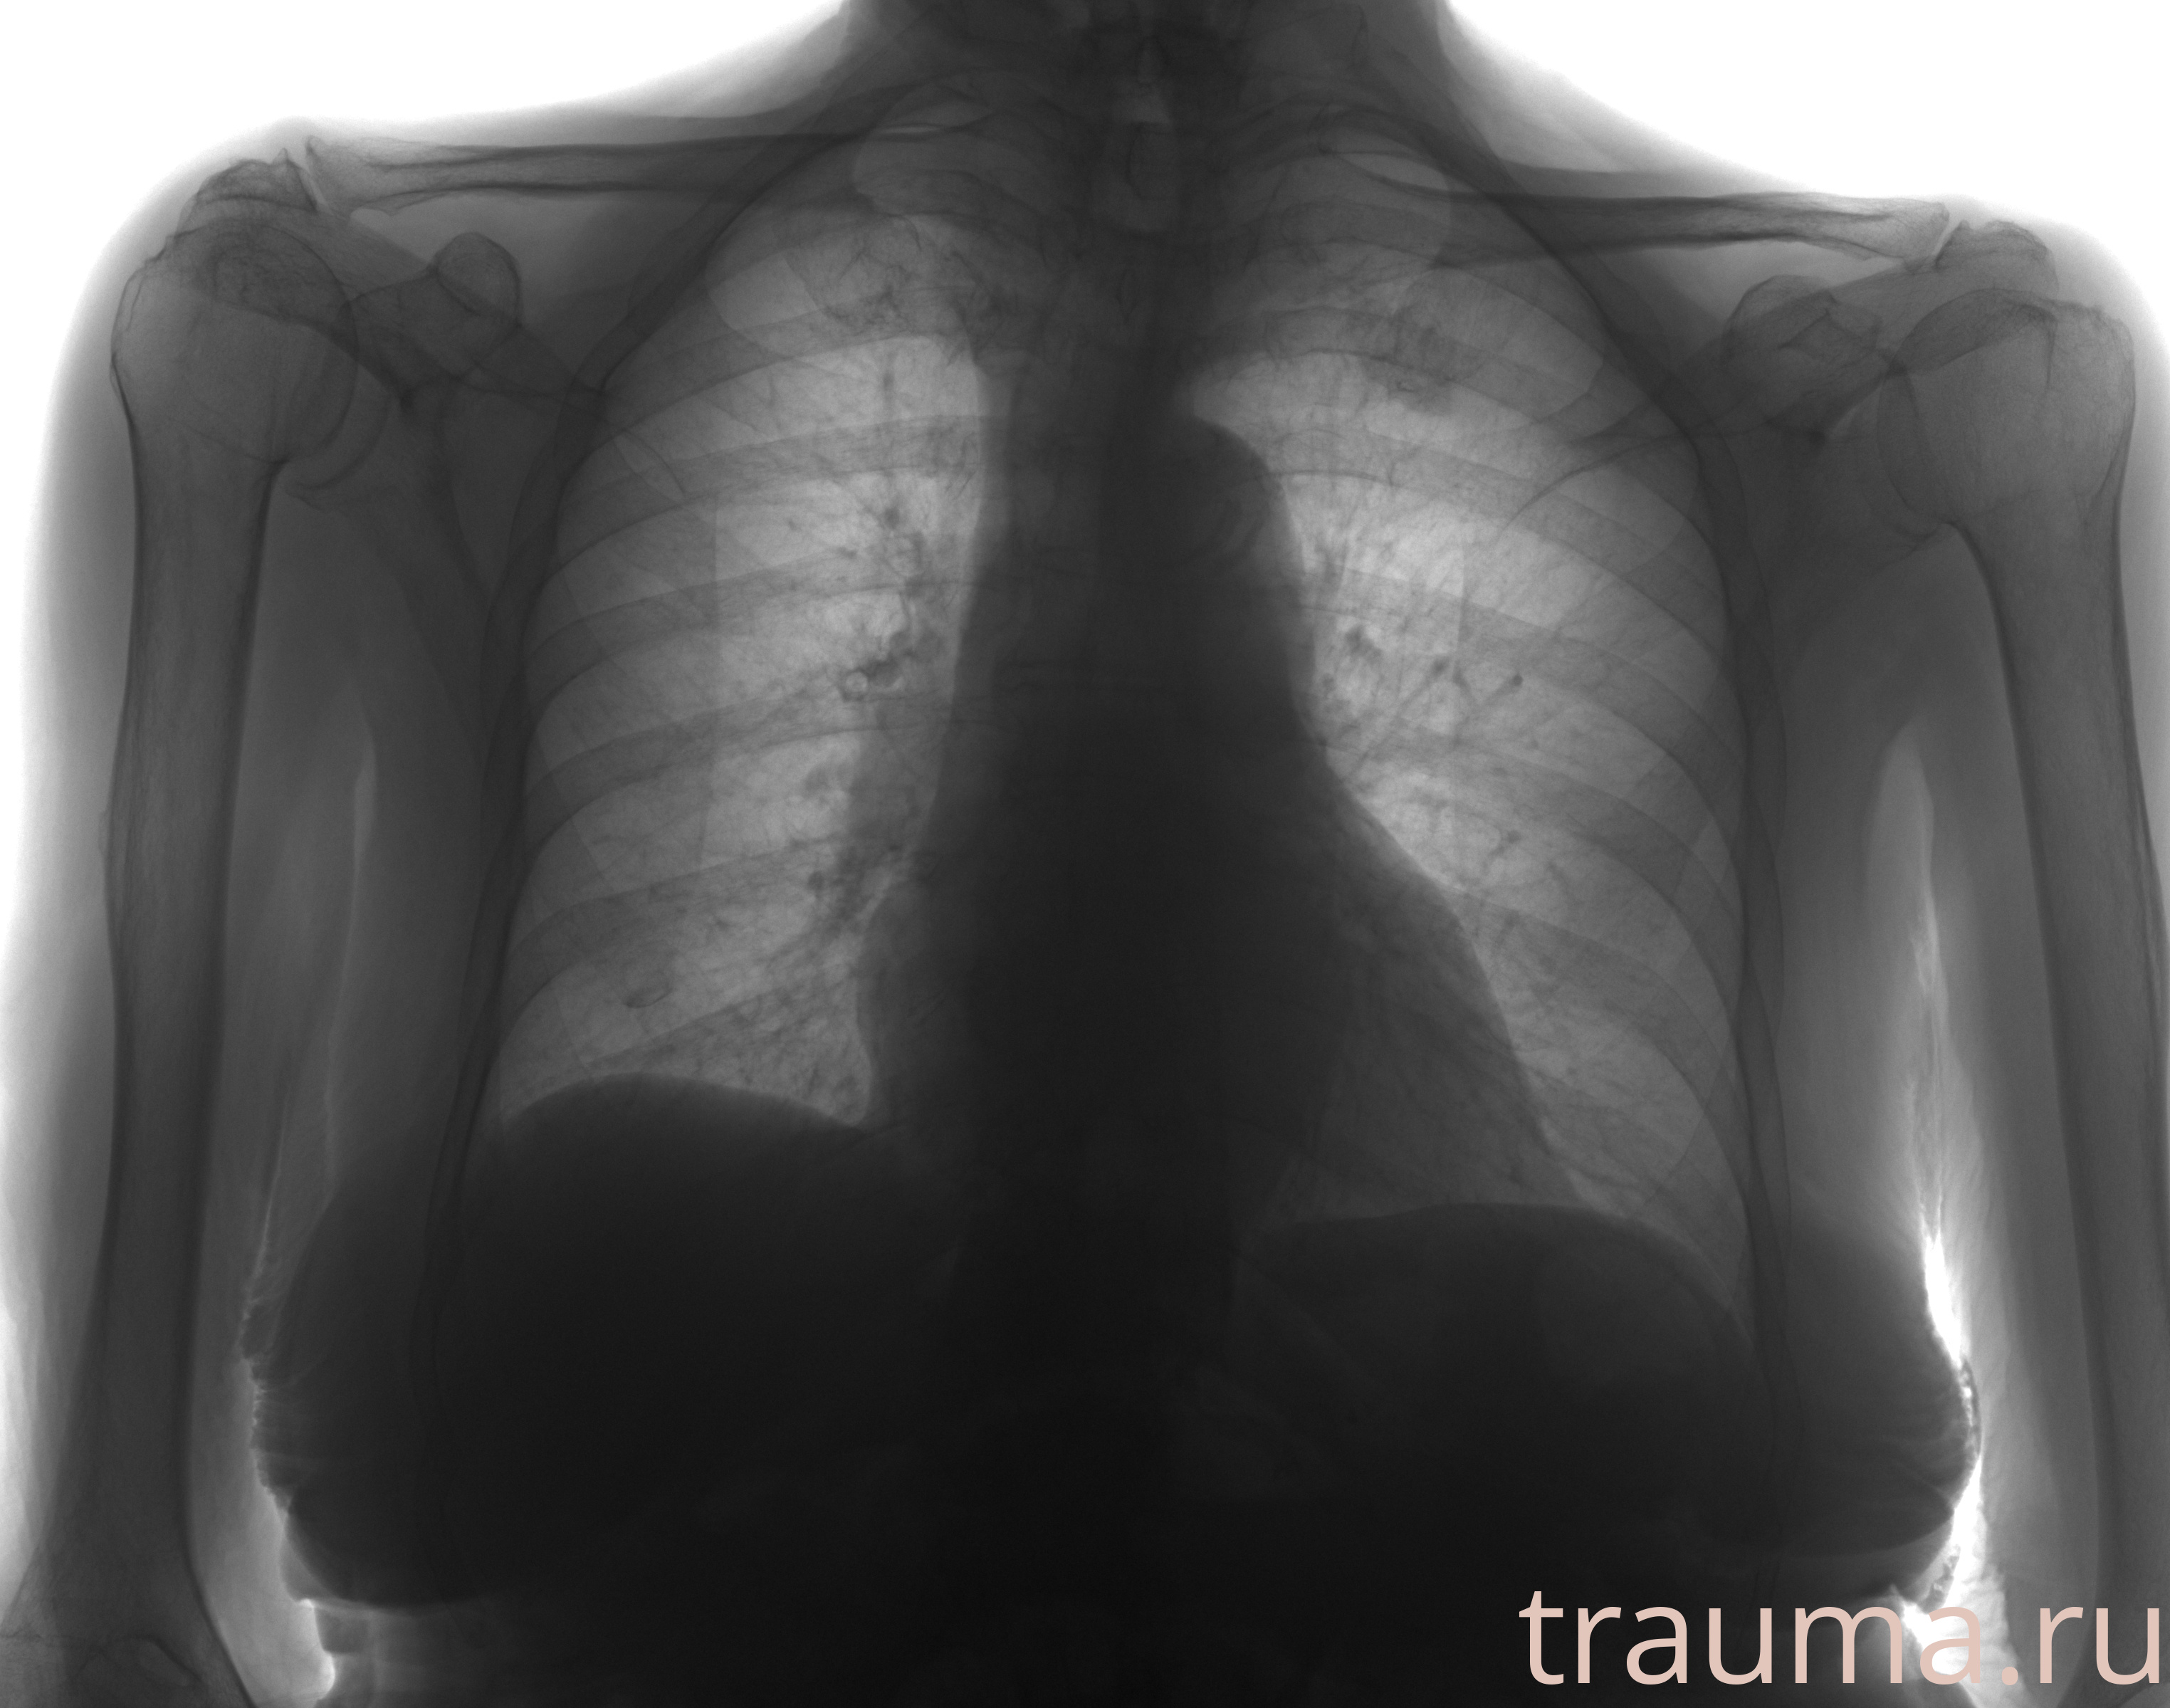

Рентген на дому: по вашему адресу приезжает врач-рентгенолог, травматолог-ортопед с мобильным рентгеновским аппаратом, проводит диагностику травмы или заболевания, делает необходимые рентгенограммы, дает рекомендации по дальнейшему лечению. Получить качественные снимки в домашних условиях возможно благодаря уникальной методике, разработанной МосРентген Центром для института  Склифосовского